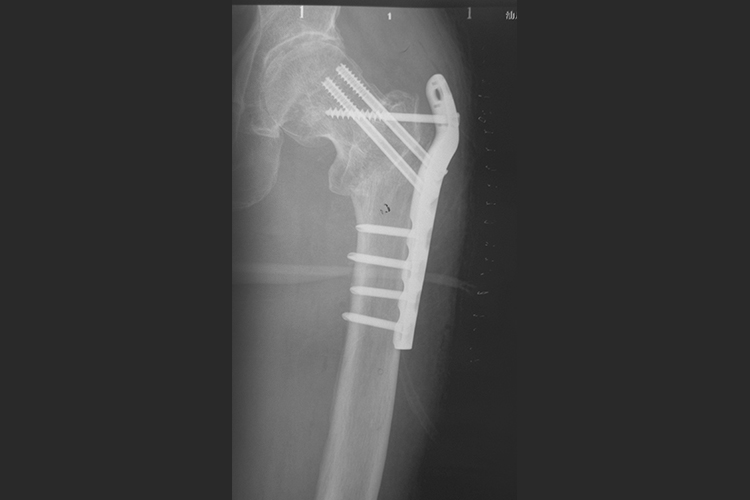

股骨近端骨折多为间接暴力导致,患者可出现髋部疼痛、下肢活动受限、不能站立和行走等症状。股骨近端钢板治疗可以使骨折块间达到加压固定。其中螺钉与钢板具有成角稳定性,相当于内支架,对骨膜的损伤更小,螺钉松动发生率更低,固定强度明显增加,因此可有效避免骨折复位再移位或复位丢失。钢板固定后,X线可明显见到钢板的形状,呈高密度影。